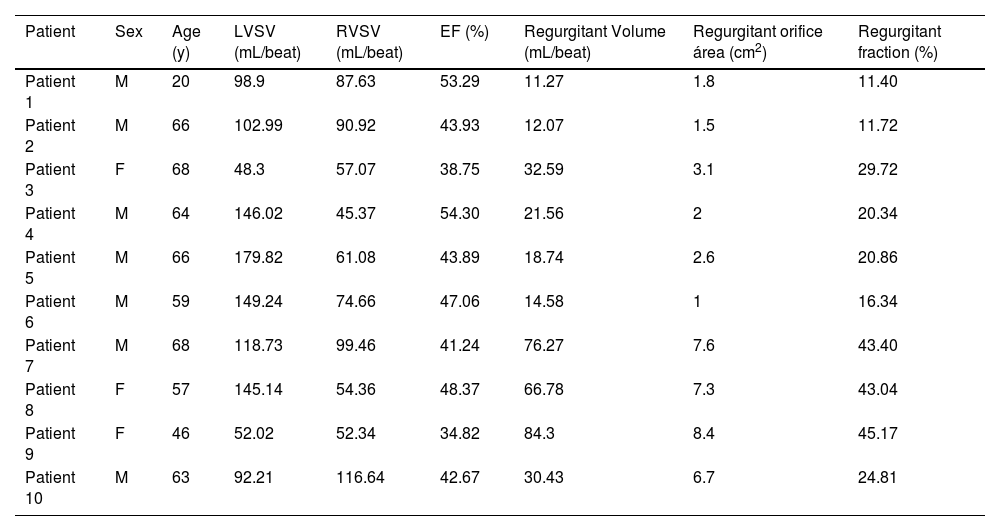

Distributions of FAPI uptake in patients with DMVRThe results from the polar map of cardiac PET images from the patients with DMVR indicated that the distribution of FAPI uptake was multifocal and irregular in the myocardial segments, with no significant differences in FAPI uptake (SUVmean) between individual myocardial segments (Fig. 5A‒C). However, for each DMVR patient, the sum of the SUVmean of FAPI uptake within segments attached to the annulus of the mitral valve and papillary muscles (basal inferoseptal, basal inferior, mid inferior, and mid anterolateral walls) was significantly higher than that in the other myocardial segments (p ˂ 0.05) (Fig. 5D). Moreover, comparison between patients with DMVR and controls revealed significantly higher FAPI-uptake (SUVmean) in the basal inferoseptal, basal inferior, mid inferior, and mid anterolateral wall segments of individuals with DMVR (1.92 ± 0.28 vs. 1.04 ± 0.06 in the basal inferoseptal wall, 1.94 ± 0.30 vs. 0.98 ± 0.05 in the basal inferior wall, 2.12 ± 0.39 vs. 1.02 ± 0.21 in the mid inferior wall, and 1.97 ± 0.33 vs. 0.96±0.05 in the mid anterolateral wall; all p < 0.01; Fig. 5E).

Images in a 63-year-old man with Mitral Valve Regurgitation (MVR) (A and B). 18F-AlF-FAPI PET images, MR images, and PET/MR fusion images in short-axis, vertical long-axis, and horizontal long-axis cine (A). The distribution of FAPI uptake in the polar map of PET images (B). There were higher FAPI uptakes in the middle myocardium, especially in the mid anterior, mid inferior and mid anterolateral wall. The uptakes of FAPI in each myocardial segment in the polar map of PET images from all participants with MVR (C). The value of SUVmean of FAPI-uptakes in each segment was represented by the width of each color bar. It showed that for each participant with MVR, there were no significant differences in FAPI-uptakes between each myocardial segment. The comparison of SUVmean between two parts of all myocardial segments in each participant with MVR (D). In each participant, SUVmean of FAPI uptakes in the part of myocardial segments, including basal inferoseptal, basal inferior, mid inferior and mid anterolateral wall, was higher than that in the other part including the remaining myocardial segments. The comparison of SUVmean in the basal inferoseptal, basal inferior, mid inferior and mid anterolateral wall between all participants with MR and normal ones (E). There was significant differences in SUVmean of each myocardial segments between them. The correlation analysis between percentage of wall thickening and SUVmean in the all myocardial segments from MVR participants (F). The correlation analysis between the peak circumferential, short and long-axis radial strains and displacements and SUVmean in the all myocardial segments from MVR participants (G‒K). The comparison of the peak circumferential, longitudinal, long-axis radial and short-axis radial strains in the basal inferoseptal (L), basal inferior (M), mid inferior (N) and mid anterolateral wall (O) between all participants with MR and normal ones. Each column represents mean ± SD. Asterisks indicate significant differences between them. *p < 0.05, **p < 0.01, ***p < 0.001.

Analysis of short-axis CMR polar maps revealed a significant negative correlation between the percentage of systolic LV wall thickening and FAPI uptake (SUVmean) in all myocardial segments of DMVR patients (r = -0.198, p = 0.012; Fig. 5F). Moreover, the peak circumferential and short-axis radial strains and displacement of the corresponding orientation in all myocardial segments were inversely correlated with FAPI (SUVmean). The results were as follows: peak circumferential and short-axis radial strains, r = 0.393, p < 0.001 and r = -0.417, p < 0.001, and circumferential and short-axis radial displacement, r = -0.207, p = 0.008 and r = -0.338, p < 0.001 (Fig. 5G‒J). Although the peak long-axis radial strains in all myocardial segments were inversely correlated with the SUVmean of FAPI (r = -0.206, p = 0.024), no significant correlation was observed between the long-axis radial displacement and SUVmean of FAPI (Fig. 5K).

In addition, data from the basal inferoseptal, basal inferior, mid inferior and mid anterolateral walls from the short-axis view of CMR images revealed significant differences in the peak circumferential strains in both the basal inferoseptal and basal inferior walls between patients with DMVR and healthy controls (-14.74 ± 2.55 vs. -9.58 ± 1.66 and -16.51 ± 1.96 vs. -11.11 ± 2.35; all p < 0.05). Comparison between DMVR patients and controls revealed significantly lower peak longitudinal strains in both the mid inferior (-12.24 ± 2.50 vs. -22.10 ± 3.92) and mid anterolateral wall segments of DMVR patients (-10.33 ± 1.36 vs. -23.30 ± 3.59; p < 0.05; Fig. 5L‒O).

Correlation of SUVmean in the myocardial segments of high FAPI uptake with MVR parametersPositive correlations were observed between SUVmean of FAPI and regurgitant volume, regurgitant fraction, and regurgitant orifice area in the basal inferoseptal and basal inferior segments. Conversely, a negative correlation was observed between SUVmean of FAPI and ejection fraction within these segments. These results were as follows: r = 0.723, p = 0.018 and r = 0.806, p = 0.008 for regurgitant orifice area in the basal inferoseptal and basal inferior segments; r = 0.717, p = 0.020 and r = 0.733, p = 0.021 for regurgitant volume in the basal inferoseptal and basal inferior segments; r = 0.796, p = 0.006 and r = 0.806, p = 0.008 for regurgitant fraction in the basal inferoseptal and basal inferior segments; and r = -0.626, p = 0.047, and r = -0.733, p = 0.021 for ejection fraction in the basal inferoseptal and basal inferior segments (Fig. 6A‒H and Table 3). However, the SUVmean of FAPI in the mid-inferior and mid-anterolateral segments was not significantly correlated with these parameters of mitral regurgitation (all p < 0.05; Fig. 6I‒P).

The Characteristics of participants’ sex, age and examinations of CMR in 10 participants with DMVR.

| Patient | Sex | Age (y) | LVSV (mL/beat) | RVSV (mL/beat) | EF (%) | Regurgitant Volume (mL/beat) | Regurgitant orifice área (cm2) | Regurgitant fraction (%) |

|---|---|---|---|---|---|---|---|---|

| Patient 1 | M | 20 | 98.9 | 87.63 | 53.29 | 11.27 | 1.8 | 11.40 |

| Patient 2 | M | 66 | 102.99 | 90.92 | 43.93 | 12.07 | 1.5 | 11.72 |

| Patient 3 | F | 68 | 48.3 | 57.07 | 38.75 | 32.59 | 3.1 | 29.72 |

| Patient 4 | M | 64 | 146.02 | 45.37 | 54.30 | 21.56 | 2 | 20.34 |

| Patient 5 | M | 66 | 179.82 | 61.08 | 43.89 | 18.74 | 2.6 | 20.86 |

| Patient 6 | M | 59 | 149.24 | 74.66 | 47.06 | 14.58 | 1 | 16.34 |

| Patient 7 | M | 68 | 118.73 | 99.46 | 41.24 | 76.27 | 7.6 | 43.40 |

| Patient 8 | F | 57 | 145.14 | 54.36 | 48.37 | 66.78 | 7.3 | 43.04 |

| Patient 9 | F | 46 | 52.02 | 52.34 | 34.82 | 84.3 | 8.4 | 45.17 |

| Patient 10 | M | 63 | 92.21 | 116.64 | 42.67 | 30.43 | 6.7 | 24.81 |

M, Male; F, Female; LVSV, Left Ventricular Stroke Volume; RVSV, Right Ventricular Stroke Volume; EF, Ejection Fraction.

Regurgitant Volume (mL/beat) = LVSV (mL/beat) - RVSV (mL/beat).

Regurgitant fraction (%) = Regurgitant Volume (mL/beat) / LVSV (mL/beat) × 100%.

Distributions of FAPI abnormality and plausible mechanisms in DMVRIn the DMVR group, the distribution of FAPI uptake showed a distinct pattern. The results from the polar maps of the short-axis view of cardiac PET images indicated that although segments of FAPI-uptakes showed multifocal and irregular, with common high uptake areas located at the valve annulus and papillary muscles (basal segments and midwall segments), indicating that MVR induces focal LV remodeling and fibrosis.

In addition, changes in the percentages of systolic LV wall thickening, circumferential and short-axis radial strains, and displacements of the corresponding orientation were negatively correlated with FAPI uptake. Variations in these strains were observed at the valve annulus and papillary muscles. The altered organization of the extracellular matrix is the common structural hallmark of degenerative mitral regurgitation. Degenerative mitral regurgitation can be classified into fibroelastic deficiency and myxomatous degeneration.21 Concurrent with leaflet alterations, patients with degenerative mitral regurgitation often exhibit severe mitral valve annular abnormalities, including annular dilatation and disjunction. These anatomical annular alterations lead to abnormal annular displacement, characterized by outward movement during late systole, termed as functional prolapse. Additionally, annular flattening increases the stress applied to the leaflets and chordae tendineae.22 Normally, the motion of the mitral annulus is passive and determined by the contraction and relaxation of the adjacent atrial and ventricular musculature. Consequently, under normal conditions, the posterior mitral ring and its adjacent myocardium move downward and anteriorly during systole, synchronizing with the remainder of the LV. In contrast, patients with mitral valve prolapse exhibit a peculiar functional abnormality of the mitral annulus (i.e., unusual systolic curling of the posterior mitral ring on the adjacent myocardium). The systolic movement of the ring was primarily downward with little, if any, anterior motion, resulting in a curled appearance in real-time motion, which may increase the circumferential strains of the mitral ring and adjacent myocardium. The presence of a systolic curling motion may contribute to the paradoxical increase in the mitral valve annulus diameter during systole, myxomatous degeneration of the leaflets, and myocardial stretch in the LV inferobasal wall and papillary muscles with relative hypertrophy and fibrosis.23 The increased longitudinal distance between the mitral valve and papillary muscles in degenerative mitral regurgitation decreases the longitudinal myocardial strains of the papillary muscles and its adjacent myocardium in systole. Chronic abnormal hemodynamic alteration induced by mitral regurgitation aggravates LV cardiac tissue remodeling and increases interstitial fibrosis, increasing the susceptibility of fibrosis in the papillary muscles and valve annulus.22 These factors directly contributed to the development of LVMD.

The European and American guidelines for the definition of severe mitral regurgitation use regurgitant orifice area, regurgitant volume, and regurgitant fraction for quantification and risk stratification.24,25 However, their clinical utility is limited.26 Given the intrinsic relationship between the basal inferoseptal, basal inferior, mid inferior and mid anterolateral myocardial segments and the anatomic locations of papillary muscles and valve annulus and their increased susceptibility to fibrosis in mitral regurgitation, the correlations between these parameters and SUVmean of FAPI in these myocardial segments were analyzed. Notably, FAPI uptake and regurgitant volume, regurgitant fraction, regurgitant orifice area and ejection fraction demonstrated strong correlations in the basal inferoseptal and basal inferior segments These findings indicate that myocardial fibrosis in these two segments could directly impact mitral valve function. Notably, FAPI uptake in the basal inferoseptal and basal inferior segments serves as a potential surrogate marker for additional risk stratification and regurgitation quantification in degenerative mitral regurgitation.

ConclusionsThe uptake of 18F-labeled AlF-FAPI in injured myocardial tissues accurately detected fibrosis in CAD and DMVR patients with LVMD. Moreover, there were different patterns of FAPI uptake distribution in the LV of patients with DMVR and CAD. The basal inferoseptal, basal inferior, mid inferior, and mid anterolateral segments were more susceptible to fibrosis in patients with DMVR, and SUVmean in the basal inferoseptal and basal inferior segments accurately assessed mitral valve dysfunction.